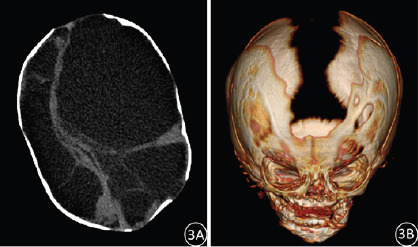

Results: At birth, the primitive reflexes were generally preserved in these infants, who exhibited a spectrum of symptoms including progressive enlargement of head circumference, epilepsy, cerebral palsy, intellectual disability, developmental delay, lethargy, convulsive spasms, and varying degrees of visual and auditory impairment. These infants may also present with other congenital malformations or abnormalities. The primary CT imaging findings revealed complete or near-complete absence of bilateral cerebral hemispheres, replaced by CSF. Specifically, there were 5 cases of complete absence of cerebral hemispheres, with minimal residual brain tissue observed in 17 cases. Bilateral ventricles were approximately normal in 3 cases and completely absent in 19 cases. Falx cerebri was incomplete or/and displaced in 12 cases, and 3 cases were concurrent with Dandy-Walker syndrome.

Conclusion: Hydranencephaly is a congenital disease characterized by destruction of the cerebral hemispheres. CT scan can provide accurate and reliable imaging evidence for the diagnosis of hydranencephaly.